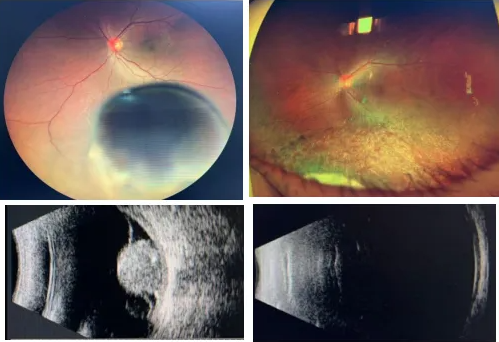

廈門眼科中心眼底病科胡欽瑞博士后為老張做了詳細且全面的檢查,眼底影像清晰顯示,他的左眼眼底有脈絡膜實性隆起,腫瘤周邊的視網(wǎng)膜還發(fā)生了滲出性脫離;B超檢查更是呈現(xiàn)出典型的“蘑菇狀”腫物——這是脈絡膜黑色素瘤的特征性表現(xiàn),結(jié)合眼底影像、超聲等檢查結(jié)果,老張左眼病變臨床診斷明確,考慮為脈絡膜黑色素瘤。